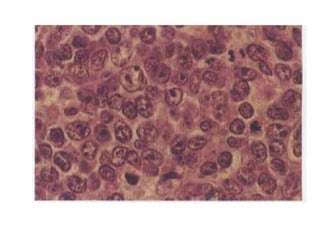

• La enfermedad se define en términos de su apariencia

microscópica (histología) y la expresión de marcadores de

superficie celular (inmunofenotipo).

• Los criterios de diagnóstico son:

• El componente de tumor. las células de Hodgkin, que son

grandes (~20 µm) con citoplasma palido relativamente

abundante, núcleo grande vesiculoso, redondeado o

irregular, membrana nuclear gruesa por marginación de

cromatina y nucléolo prominente. Las células de Reed-

Sternberg: gigantes (15-45 µm) con citoplasma abundante;

nucleo bilobulado o multinucleado grande vesiculosos

con membrana nuclear gruesa; un nucléolo prominente

eosinofilo

• El componente reactivo (linfocitos pequeños maduros

[B: alrededor de folículos, T: alrededor de ceulas RS],

eosinófilos, plasmocitos, histiocitos, células foliculares

dendríticas, neutrófilos, fibroblastos, fibras colagenas,

fibrosis y capilares).